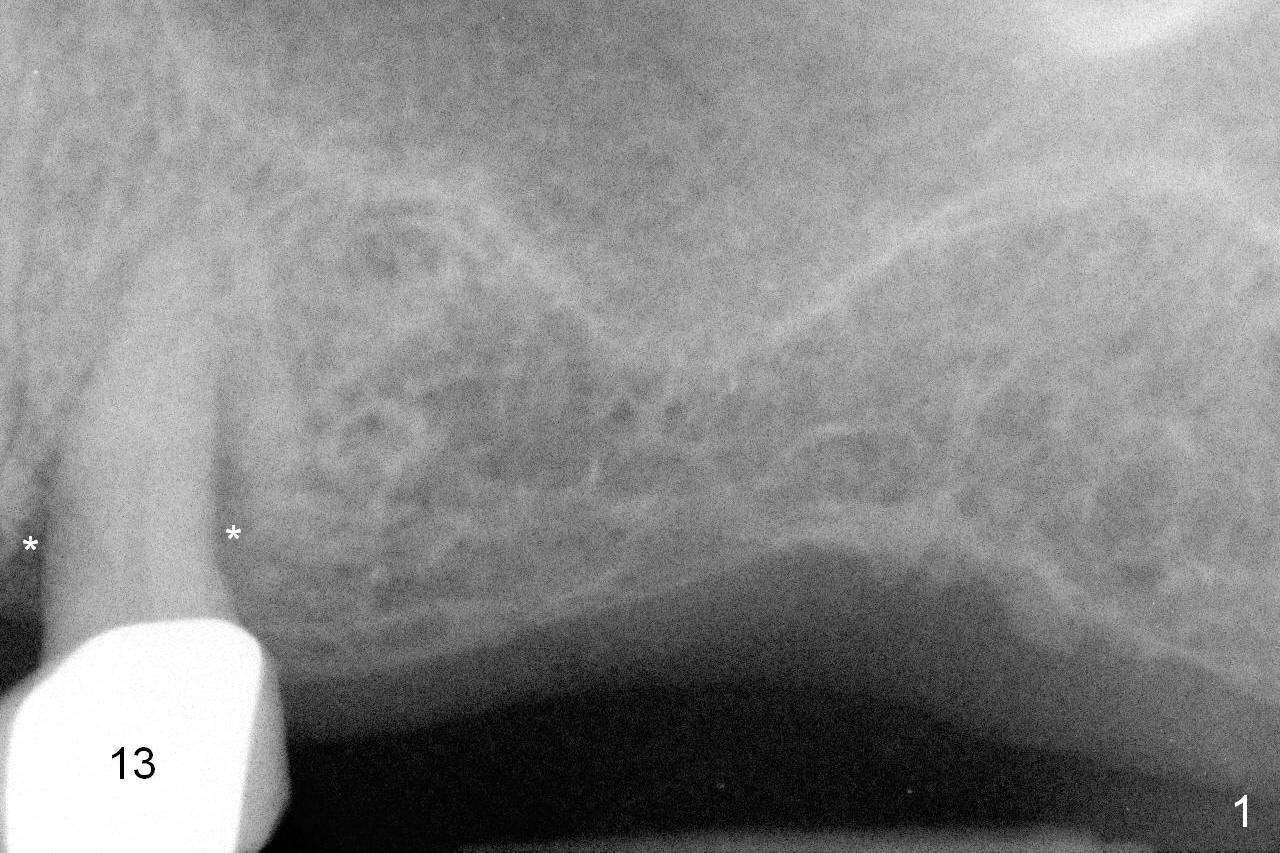

A 73-year-old woman is a possible bruxer with partial edentulism; the tooth #13 had increased periodontal ligament (pdl) space 4 years ago (Fig.1 *). A 5x14 mm tissue-level implant is placed at the site of #14 (Fig.2). The implant appears to be osteointegrated in 6 months (Fig.3). There is crestal bone loss 8 months post cementation (Fig.4 *). The persistent increased pdl at #13 is most likely associated with occlusal tramua from the tooth #19 (Fig.5 (13 months post cementation of #14)). Three years post #14 cementation, the tooth #13 has mobililty II (Fig.6); bone density increases around the apical half of the implant (arrowheads). Normally bone density is the highest coronally where functionality dictates. This indicates the bone loss is getting worse at #14 as well.